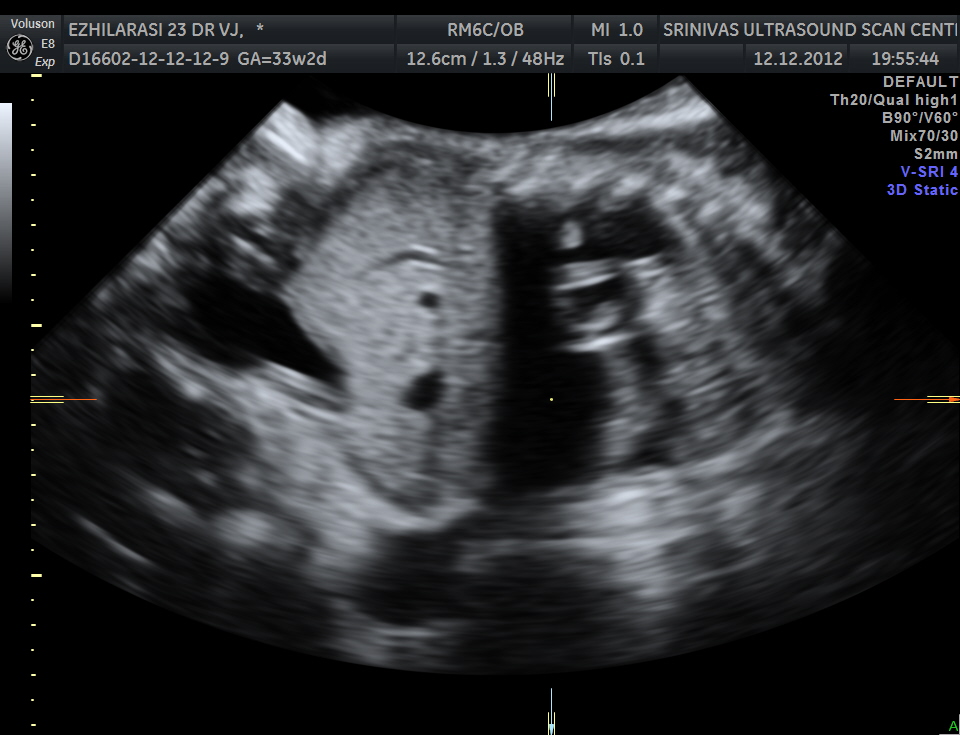

The heart was seen in the right side of thorax . The left hemithorax showed the stomach bubble and bowel loops suggestive of Congenital Diaphragmatic Hernia .

The fetus also showed bilateral pelvi calyectasis and rt ureteromegaly.